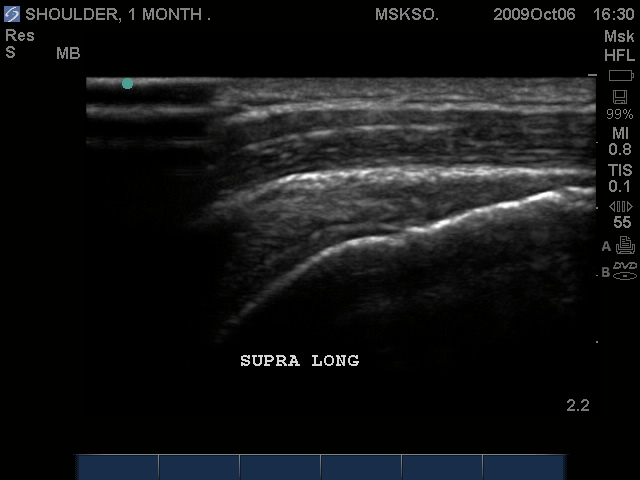

Long axis Supraspinatus tendon over lateral Greater Tuberosity. (lateral greater tuberosity is flat relative to the anterior) Tendon retraction is seen over cartilage interface sign of the humeral head.

Slightly anterior movement of the probe to visualize the full detail of the tear only for this case study purpose.